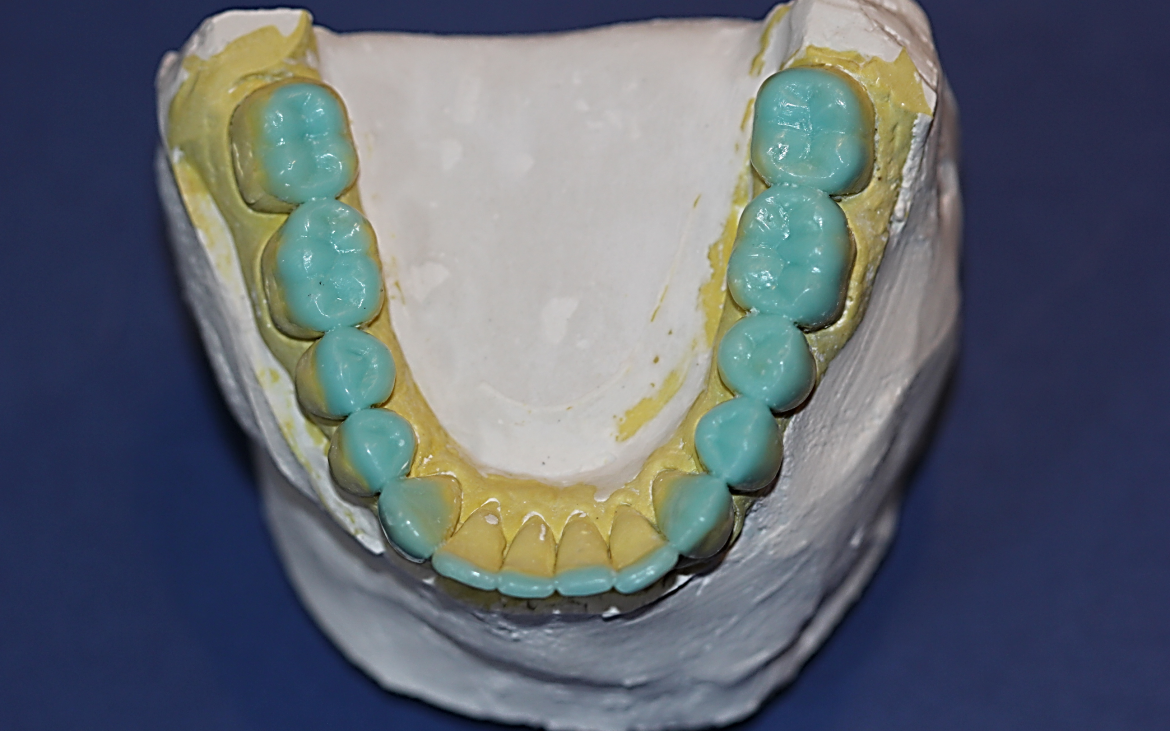

5- Ceroplastia na nova posição de máxima interiorização, recuperando 3mm da DVO com avanço mandibular de 6mm(Cêntrica longa).

Modelos montados em articulador. Registro oclusal com jig de Luís Fellipe (orientar o melhor posicionamento mandibular).

6- Ceroplastia realizada nos terço incisais dos anteriores e oclusal dos posteriores inferiores.

7. Dentes posteriores – vertentes internas rasas, formato oclusal lobular cheio valorizando sulcos principais e sulcos de escape.